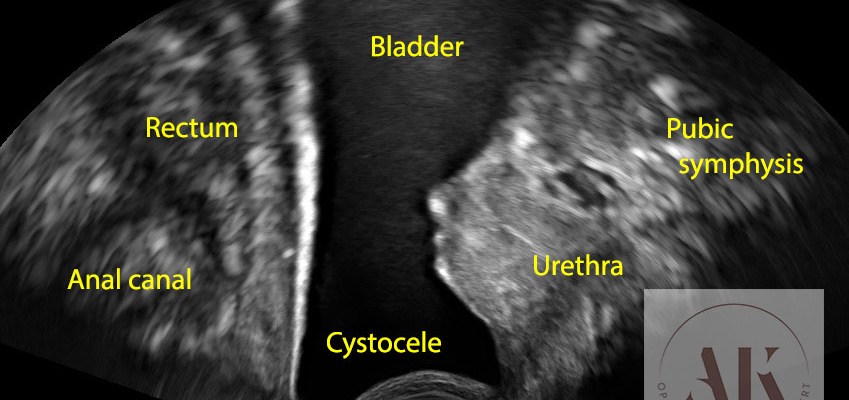

Στην πρόπτωση κύστης ή αλλιώς κυστεοκήλη, η ουροδόχος κύστη δεν αδειάζει πάντοτε όπως πρέπει, με αποτέλεσμα να δημιουργείται συνεχώς ένας μικρός υπολειπόμενος όγκος ούρων. Αυτό αποτελεί από μόνο του κίνδυνο για συχνές ουρολοιμώξεις.